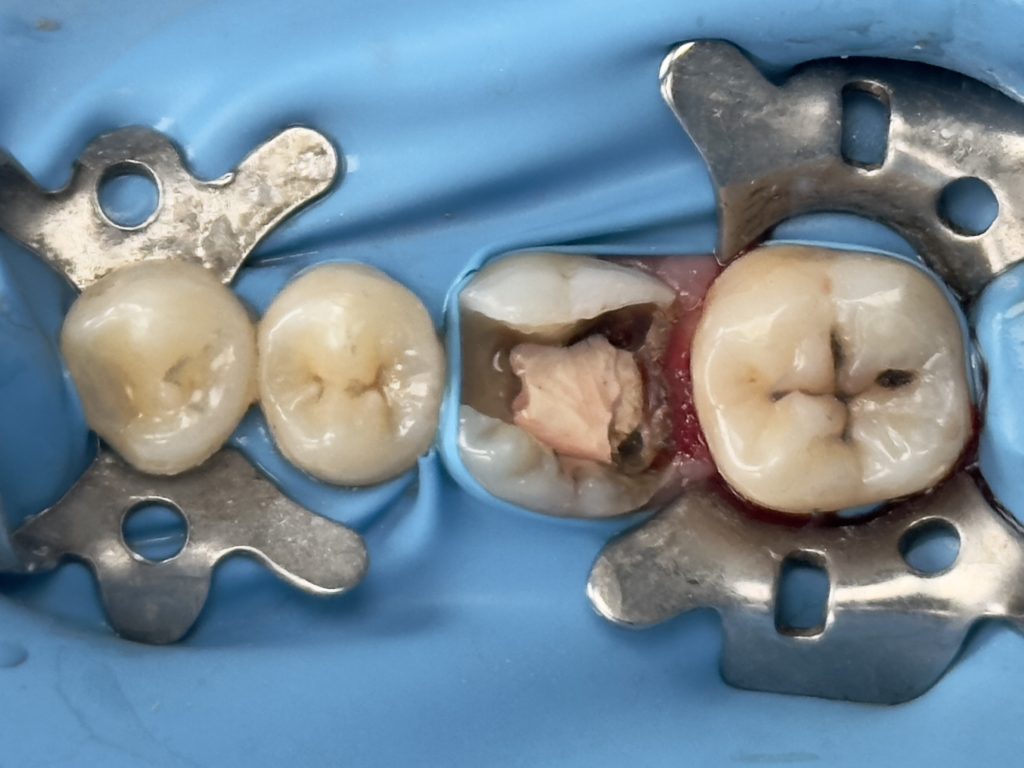

Patient (dentist) came complaining from amalgam restoration placed 3 years ago and caused multiple tooth fractures

-Complete amalgam removal

-gingival trimming of the inflamed gingival caused by over hanging margin

( tip : transfer the rubber dam strap between tooth no.6 &7 with blunt instrument to the contact between tooth no.5&6 rather than removing the entire RD sheet to trim the gingiva

then put it back to its position after the trimming) this controls the bleeding & saves time

-clean & neat margin

-IDS & RC

-DME (matrix sealed with teflon &diamond wedge)

-ever X posterior to increase fracture resistance